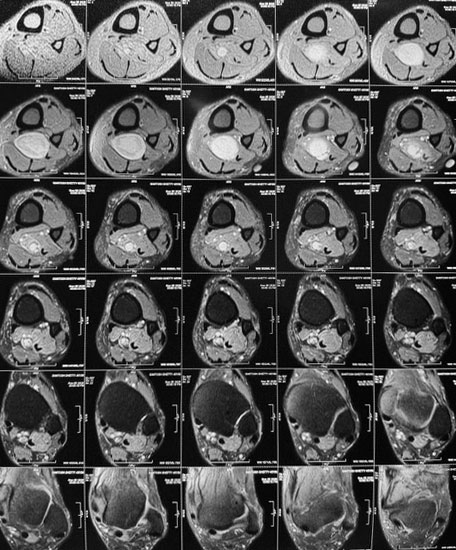

Dr. Ujwal Yeole is an experienced neurosurgeon specializes in treating a wide spectrum of neurological conditions including neuro-oncology, peripheral nerve disorders, vascular disorders, spinal pathologies, pediatric neurosurgery, neuro-trauma and skull base neuroendoscopic procedures.